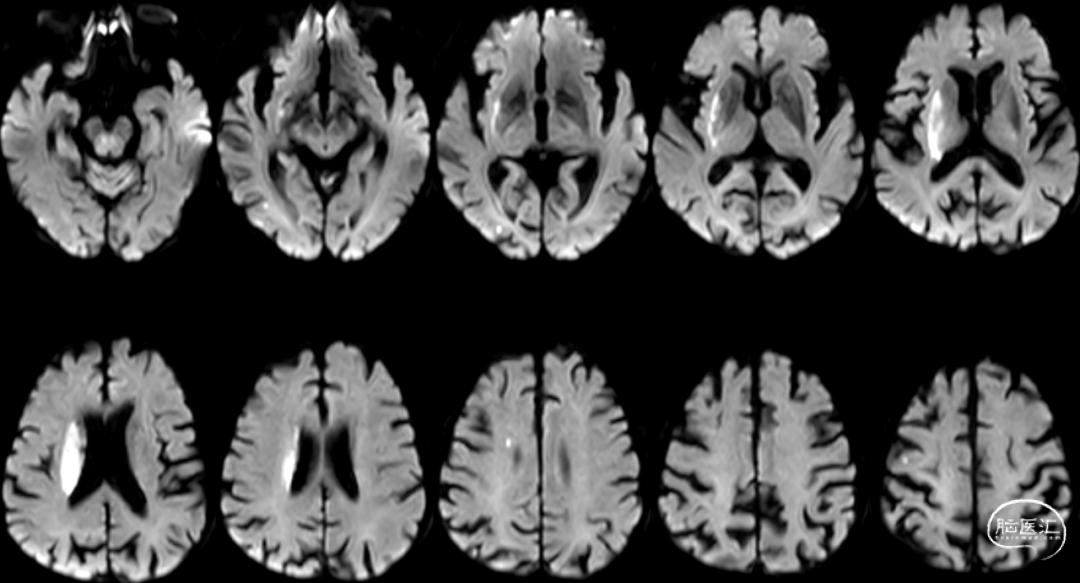

Cranial DWI:右侧壳核、侧脑室旁小片状+皮层点状弥散受限。

Cranial SWI:SVS+AHVs RMCA M1长条血栓。

T2 Flair:丰富的高信号血管征(HVS)。

Reexamination Cranial DWI:无明显的血栓向远端逃逸或小血栓脱落后新形成的皮层或分水岭点片状梗死。

Reexamination Cranial T2 Flair。